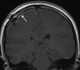

Craniotomy flap

A craniotomy is a surgical operation in which a bone flap is temporarily removed from the skull to access the brain. Craniotomies are often critical operations, performed on patients who are suffering from brain lesions or traumatic brain injury (TBI), and can also allow doctors to surgically implant deep brain stimulators for the treatment of Parkinson's disease, epilepsy, and cerebellar tremor. [Source: Wikipedia ]